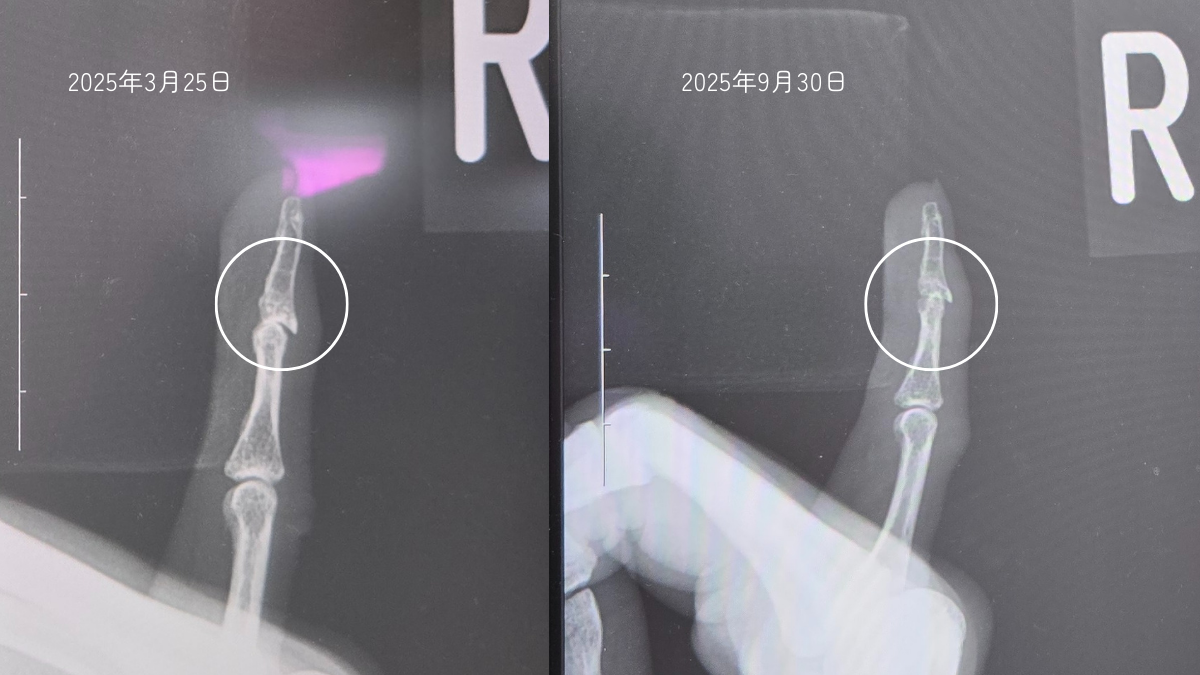

あまりに痛みが続くので、9月に再び整形外科を受診したところ、「変形の進み方が早い」と指摘され、専門医を紹介されました。

総合病院での診断結果も同じ。

「自然に治ることはなく、基本は経過観察」とのことでした。

今の強い痛みは、関節がまだ動いているから起こるのだそうです。

やがて進行が止まれば関節は動かなくなり、痛みも出なくなるとの説明を受けました。